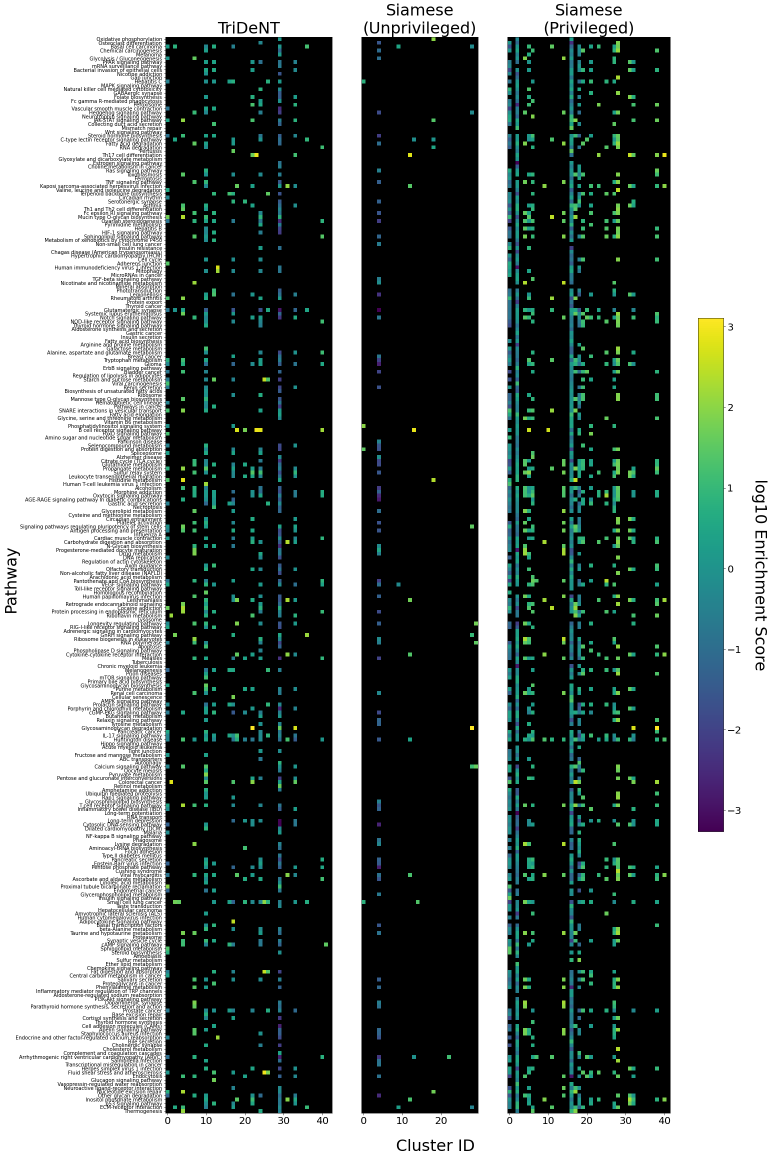

To assess the level of information shared between the transcriptomic results and the representations of the H&E patches, we investigate the cross-correlation between elements of the representations and the gene counts for each matching patch. We calculate the cross-correlation across the validation set between each element in the representations and the count for each gene, and for each gene take the correlation of the corresponding element with the maximum correlation or minimum anti-correlation, whichever has the greater absolute value. This maximum/minimum is chosen because the vast majority of elements will not correlate with any given gene, and the absolute value is taken because the sign of the element is arbitrary, so correlation and anti-correlation are equivalent. We use the absolute value of the correlation for the element selected for each gene, and use these to generate the histograms in Figure 3(a). It is clear that privileged training obtains representations which are far more correlated to the gene counts than unprivileged training, with minimal differences in the correlations between TriDeNT ♆ and Siamese approaches. This implies that the models have learned equivalently informative representations about the coarse-grained features of the genes. Figure 3(c) demonstrates that the correlation strength is significantly greater for TriDeNT ♆ compared to an unprivileged Siamese model, and Figures S3 and S4 show the relationships between the gene correlations of representations from TriDeNT ♆, Siamese methods, and supervised learning. Figures S5 and S6 show the geneset enrichment for each method, demonstrating that TriDeNT ♆ captures more meaninful interrelationships that are more informative about the relationship between tissue morphology and gene expression than unsupervised Siamese models. This is especially important for scientific discovery, as these analyses are used to generate hypotheses for further research. Figure S7 shows UMAP projections of the representation space coloured by genotype and gene, to illustrate that TriDeNT ♆ identifies distinct morphological clusters which are not found by unprivileged Siamese models. Figure 3(a) also shows that the findings are robust to human and mouse datasets, indicating the generality of the method.

To further analyse the learned representations, we produce UMAP projections of the latent space labelled with the tissue types for the NCT tissue type classification task, as shown for CD3CD20 and SMA in Figure 4(a), and for all SegPath stains in Figures S8 and S9. These figures make the reasons for the varying performance of the privileged Siamese model more apparent. For stains with better performing privileged Siamese models, such as SMA, the UMAPs are very similar between Siamese methods and TriDeNT, with well-differentiated tissue type clusters. In those with worse performance, such as ERG, the tissue types are poorly differentiated, often with only adipose and background forming distinct clusters from the other classes. On closer inspection, it is notable in these projections that TriDeNT ♆ produces more well-defined and separated clusters in general than Siamese networks. This is further evidenced in Figure S7, where TriDeNT ♆ is shown to identify clusters with overexpression of a given gene significantly more effectively than an unprivileged Siamese model.

The utility of TriDeNT ♆ for research applications can be found not only in increasing the efficacy of primary data models for prediction accuracy, but also in training models to extract coarse-grained features which are relevant to the privileged input. A typical use case is that a scientist with a paired dataset could train a model to then evaluate an unpaired dataset, without needing to acquire more paired data. We have shown that the features which are found by privileged methods are significantly different from those found by unprivileged methods. This means that TriDeNT ♆ could enable the identification of novel morphological clusters that are functionally important, such as those in our analyses in Figures 4(a) and S7, which might not emerge from other methods of training or training on the new dataset alone.